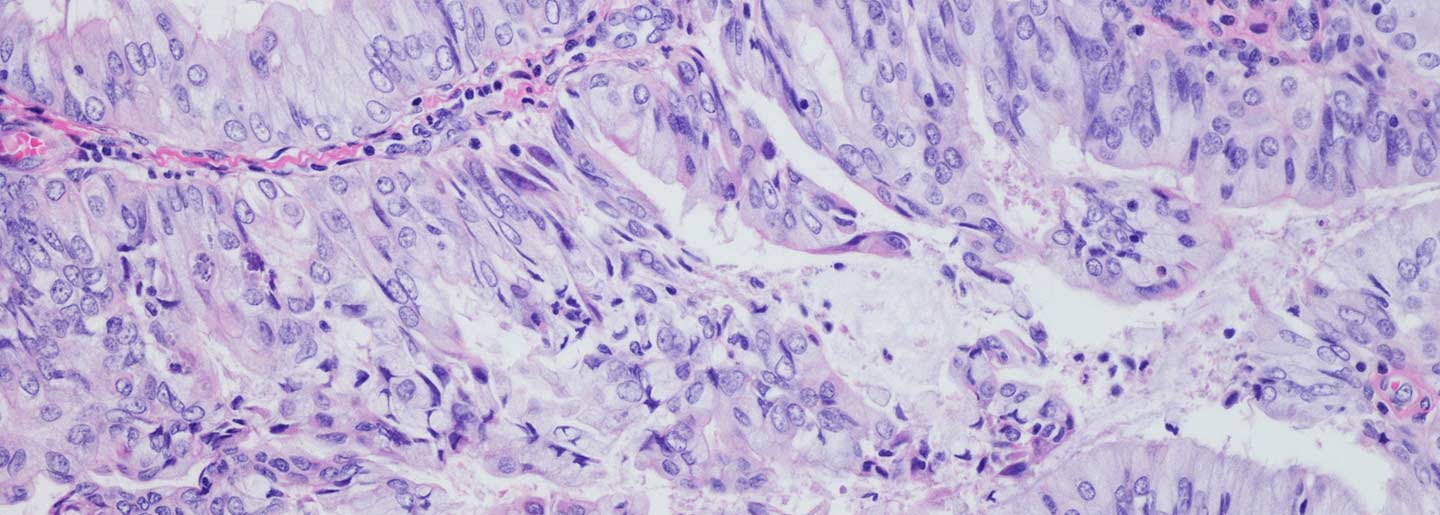

With a goal of developing new treatment strategies that take advantage of other types of immune cells, Moffitt researchers aimed to better understand the role B cells play in endometrial cancer. They analyzed 107 endometrial cancer specimens for expression of specific antibodies. They discovered that all endometrial cancer subtypes displayed expression of IgA and IgG antibodies, with most tumors having higher levels of IgA. They also found that immune cell infiltration of endometrial tumors was associated with patient outcomes according to tumor subtype. For example, higher levels of B cells were associated with better outcomes among high-grade endometrioid and serous endometrial cancer subtypes, while higher levels of T cells were associated with improved survival among clear cell endometrial cancer subtypes.